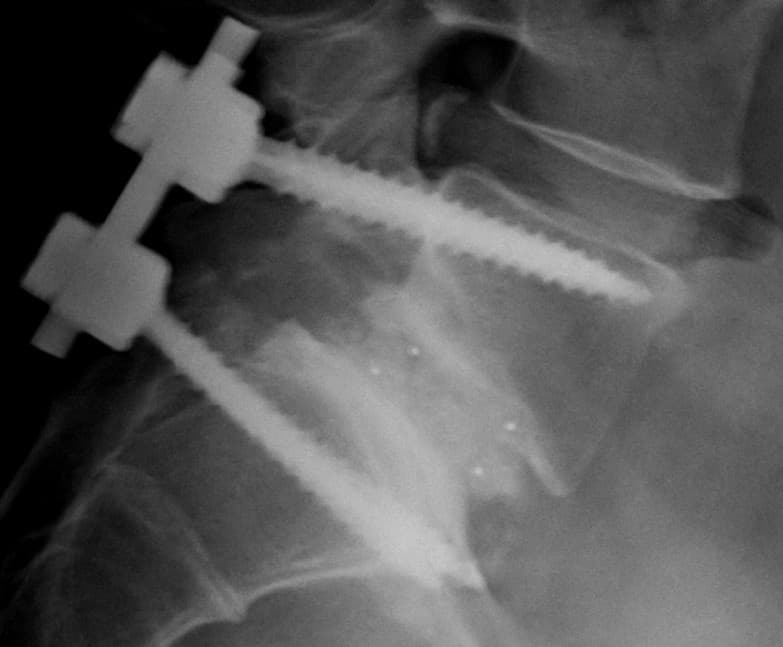

Spinal fusion, also called spondylodesis or spondylosyndesis, is a neurosurgical or orthopedic surgical technique that joins two or more vertebrae. This procedure can be performed at any level in the spine (cervical, thoracic, lumbar, or sacral) and prevents any movement between the fused vertebrae. There are many types of spinal fusion and each technique involves using bone grafting—either from the patient (autograft), donor (allograft), or artificial bone substitutes—to help the bones heal together. Additional hardware (screws, plates, or cages) is often used to hold the bones in place while the graft fuses the two vertebrae together. The placement of hardware can be guided by fluoroscopy, navigation systems, or robotics. Spinal fusion is most commonly performed to relieve the pain and pressure from mechanical pain of the vertebrae or on the spinal cord that results when a disc (cartilage between two vertebrae) wears out (degenerative disc disease). It is also used as a backup procedure for total disc replacement surgery (intervertebral disc arthroplasty), in case patient anatomy prevents replacement of the disc. Other common pathological conditions that are treated by spinal fusion include spinal stenosis, spondylolisthesis, spondylosis, spinal fractures, scoliosis, and kyphosis. Like any surgery, complications may include infection, blood loss, and nerve damage. Fusion also changes the normal motion of the spine and results in more stress on the vertebrae above and below the fused segments. As a result, long-term complications include degeneration at these adjacent spine segments. Spinal fusion can be used to treat a variety of conditions affecting any level of the spine—lumbar, cervical and thoracic. In general, spinal fusion is performed to decompress and stabilize the spine. The greatest benefit appears to be in spondylolisthesis, while evidence is less good for spinal stenosis. The most common cause of pressure on the spinal cord/nerves is degenerative disc disease.